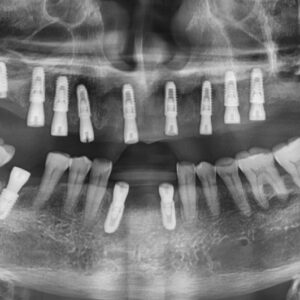

엑스레이 사진에서 보시면 양쪽 위 아래 사랑니가 모두 있고

왼쪽 아래 사랑니가 누워서 부분적으로 매복되어 있는 상태입니다.

오른쪽 아래 사랑니를 발치하고 엑스레이를 찍어 확인하였습니다.

왼쪽아래 옆으로 누워있는 사랑니도 발치를 하였습니다.